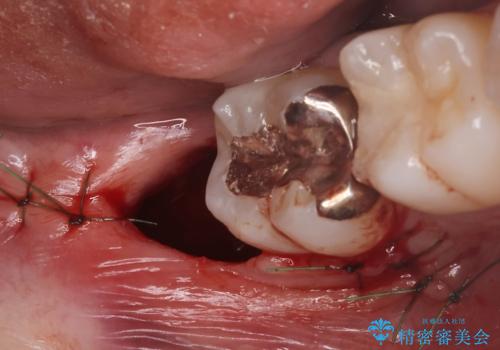

Dr. 長嶋美咲の症例写真

担当医 長嶋美咲<2025年10月17日更新>